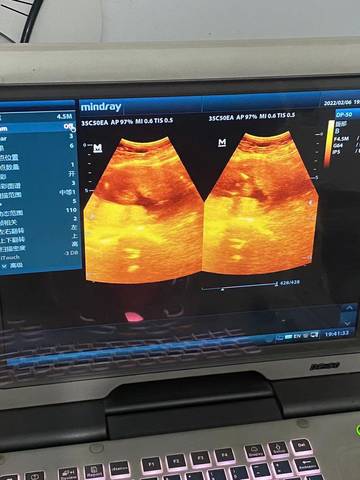

孕三胎了 今天去做彩超 我姐就拍下来了 有会看彩超单的吗?帮我看看吧 怀孕生孩子太辛苦了

journal_insert_pic_1719849578journal_insert_pic_1719849591

你好。根据数据图片看不出来的。是不科学依据的,孕期定期检查,只要宝宝健康就好。祝心想事成。

亲爱的,通过这些判断不出来的哈,反正宝宝发育好就是最好的哈,祝你心想事成。加油